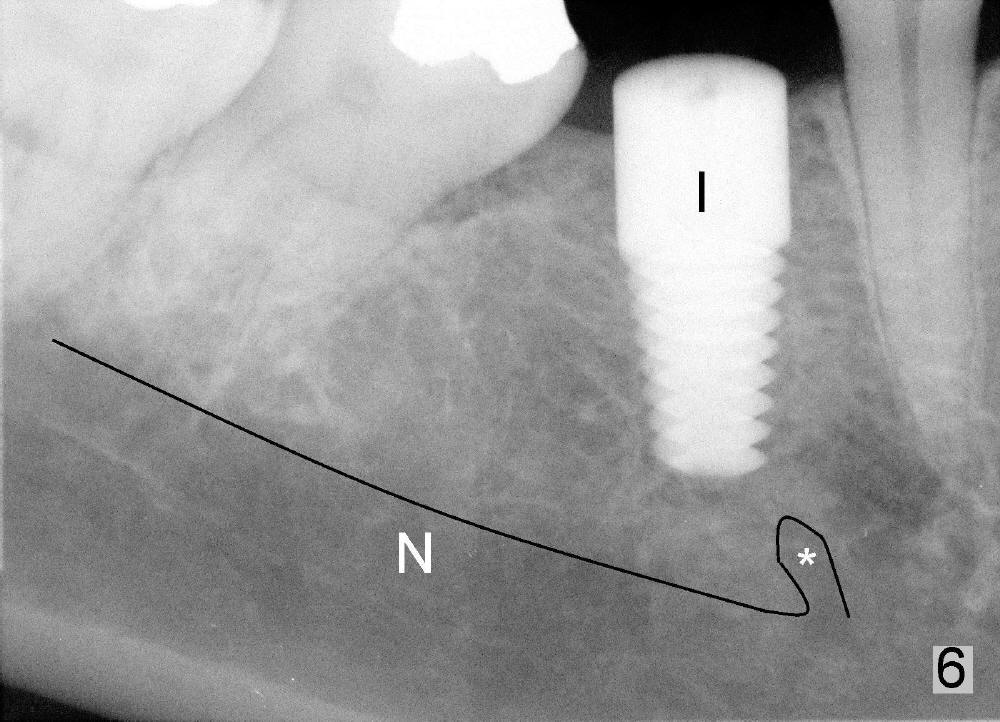

这一例由于病人条件好(骨头宽),术前准备工作充足,术中小心翼翼,最终结果还比较理想(图六):植牙(I:6x14毫米)离神经(N)以及颏神经襻(*)两到三毫米。最后缝合伤口(图七)。由于这位病人口腔卫生维持的好,第二前臼齿刷的干干净净,术后没有用抗生素。现在术后第四天还没有感染或者神经受损迹象。